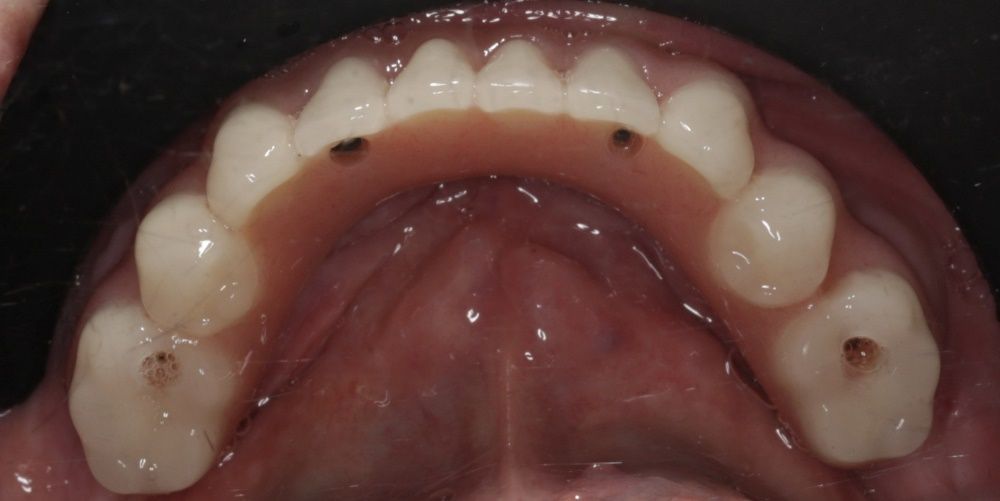

В клинике AppleStom мы регулярно проводим операции по полному восстановлению зубов с применением концепции All-on-4 — все зубы на четырёх, шести или восьми имплантатах. Это позволяет решить проблему полностью всего за один день. Вы приходите утром — а уходите с новыми зубами. Это не просто удобно, это возвращает качество жизни.

Эти операции мы любим и гордимся результатами. Пациенты получают сразу эстетичный и надёжный результат, который улучшает качество жизни. Мы хотим выполнять такие операции чаще, потому что знаем — у нас это получается на высоком уровне.

Если вы рассматриваете имплантацию всех зубов в Москве, приходите в AppleStom. Мы составим для вас подробный план лечения и покажем реальные примеры наших успешных работ.